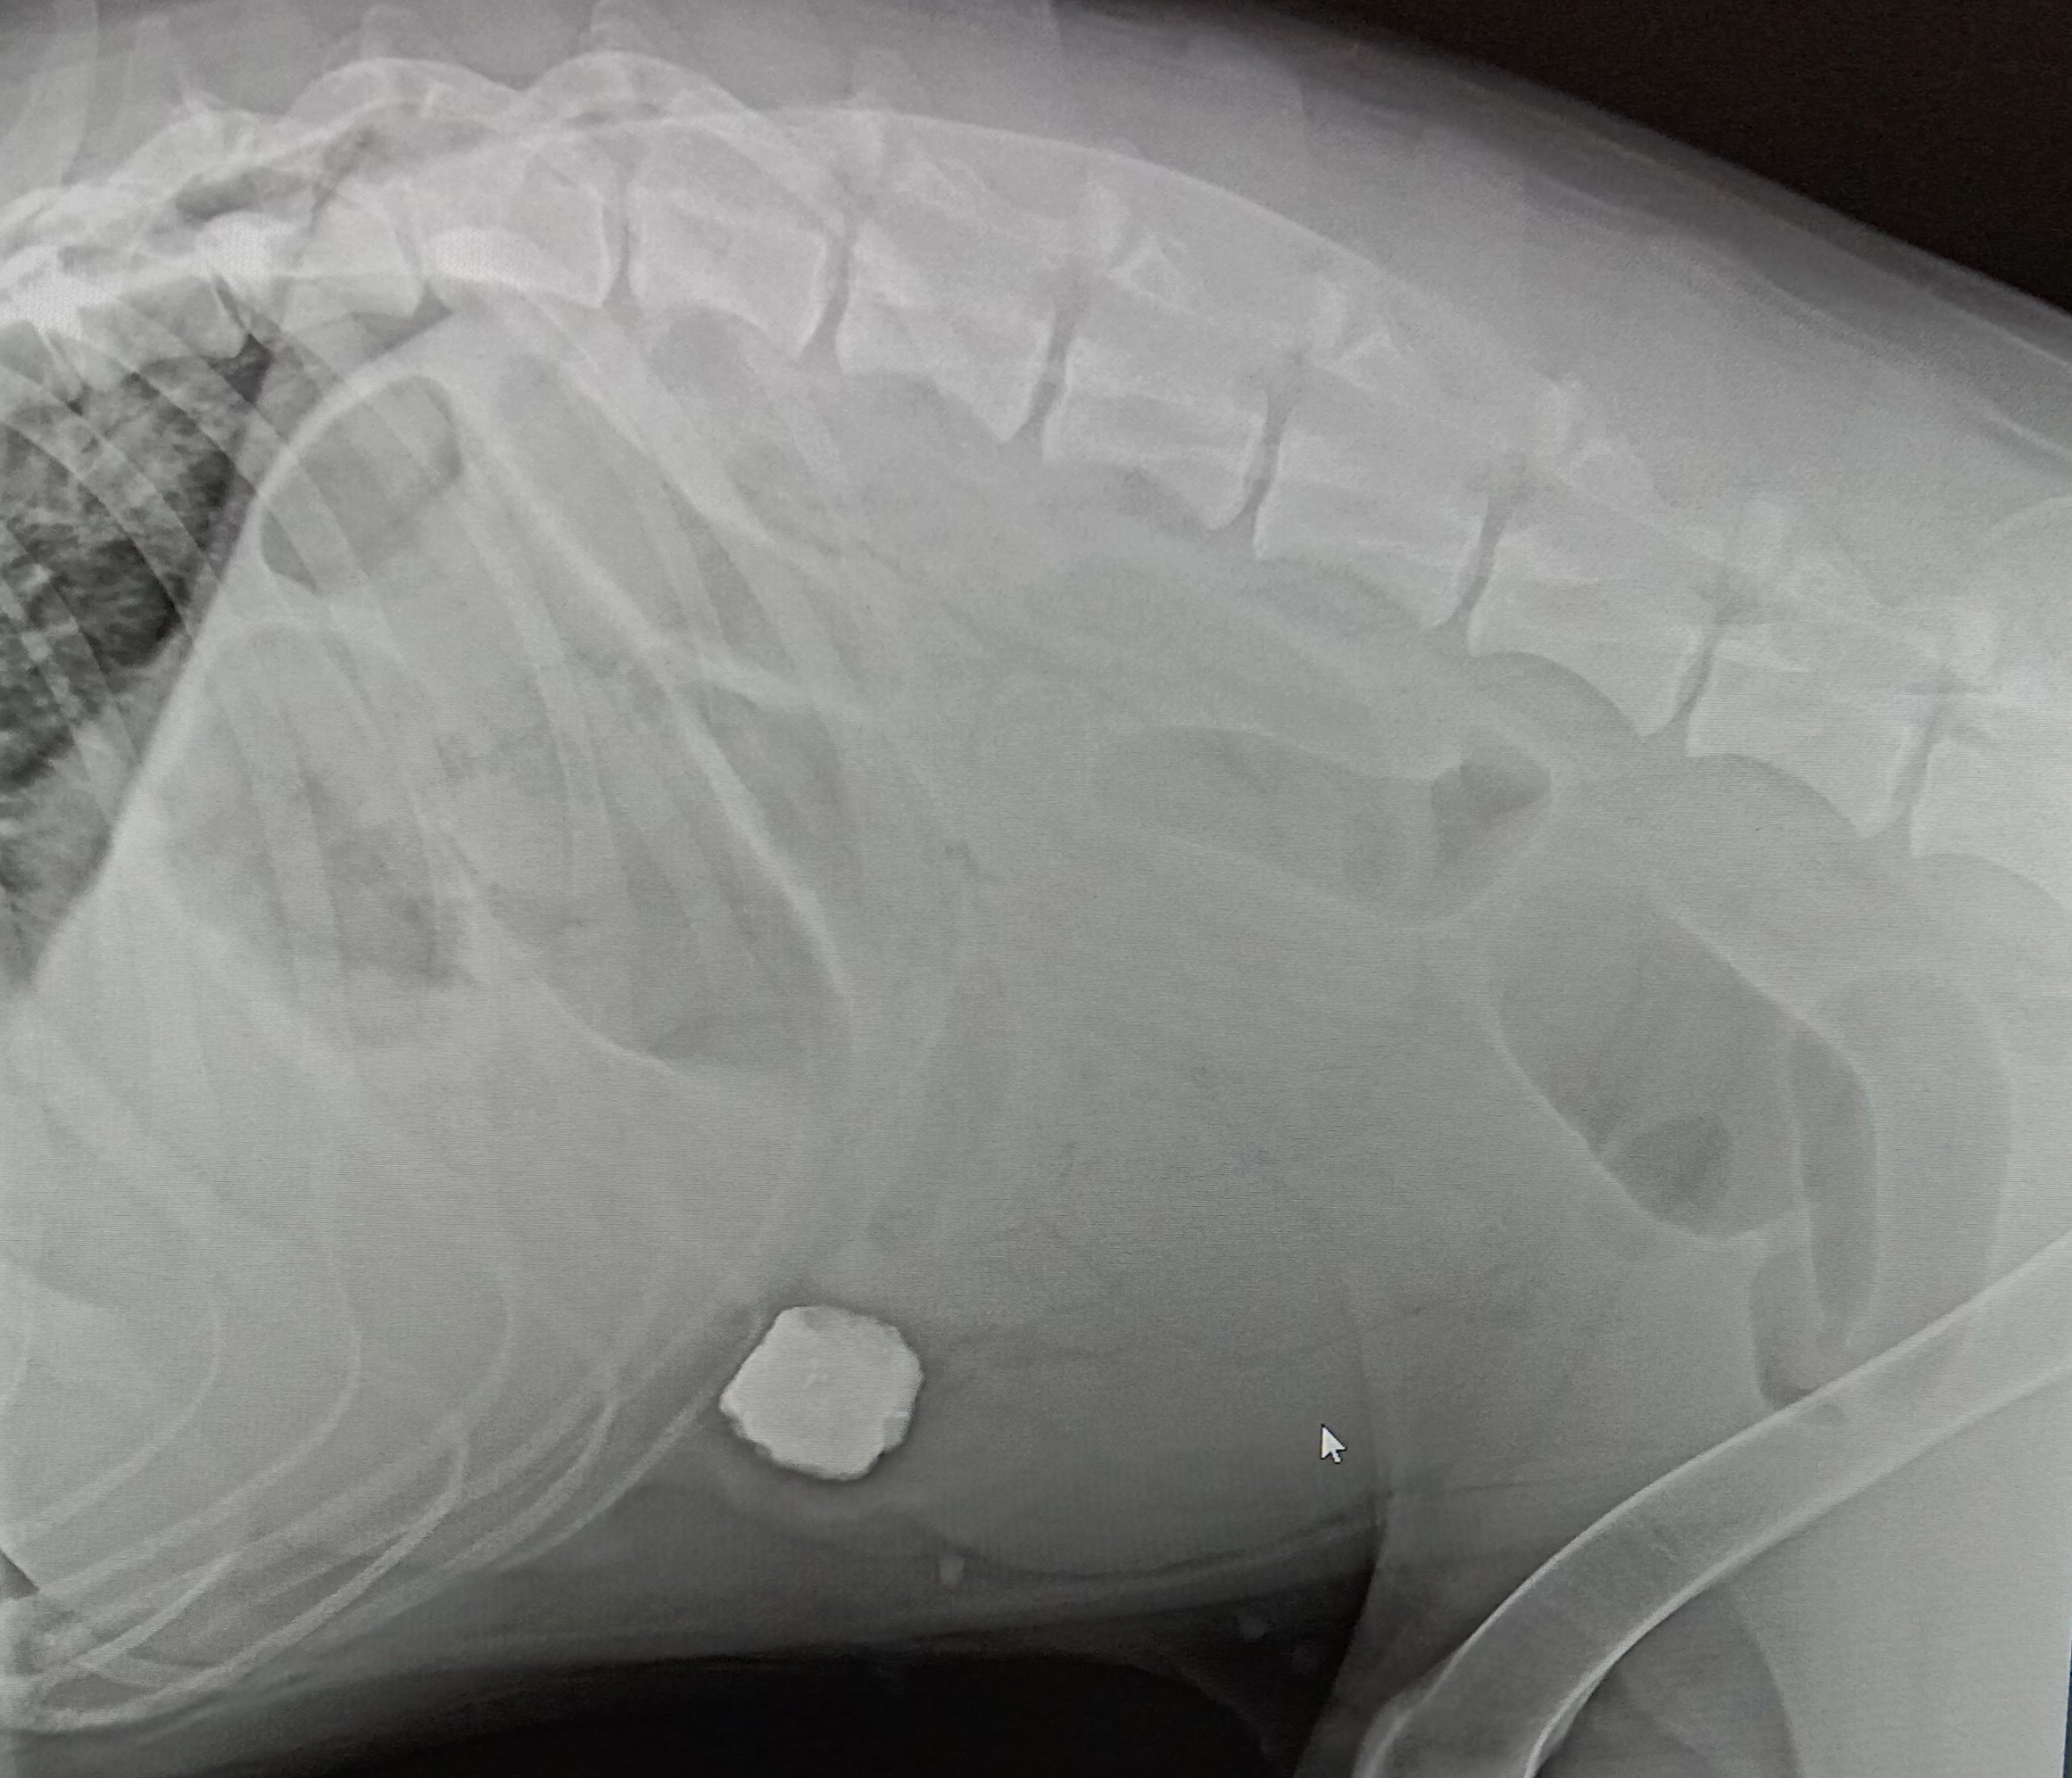

Магнитогорские ветеринары достали из кишечника собаки булыжник

Об интересном случае рассказали доктора клиники «Биовет».

Немецкую овчарку по кличке Арни хозяева привезли с жалобами на вялость, потерю аппетита и рвоту.

Врачи сделали рентгеновский снимок и обнаружили в кишечнике большой камень. Играя на улице, пес проглотил булыжник, который вместе с пищей попал в кишечник и закупорил его.

«Арни пришлось перенести срочную операцию по удалению инородного предмета. Он хорошо ее перенес, быстро вышел из наркозного сна и отправился домой. “Трофей” врачи отдали благодарным владельцам Арни», – рассказали в клинике.